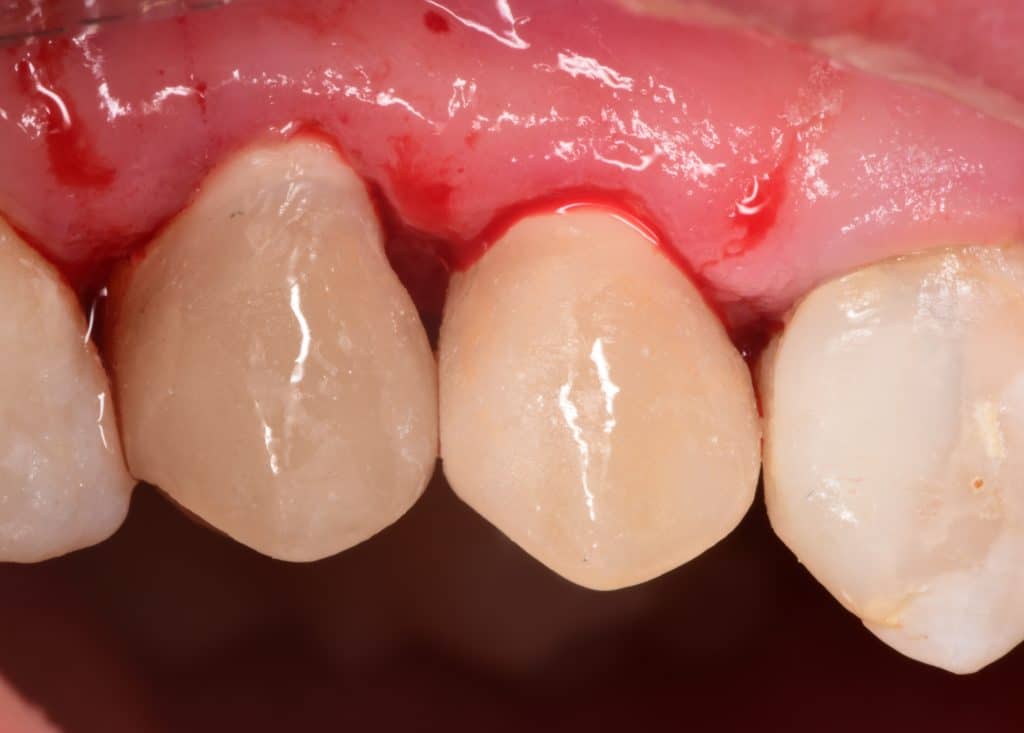

Immediate result after rubberdam removal

Immediate result, buccal view in occlusion

Before and after 2 week's